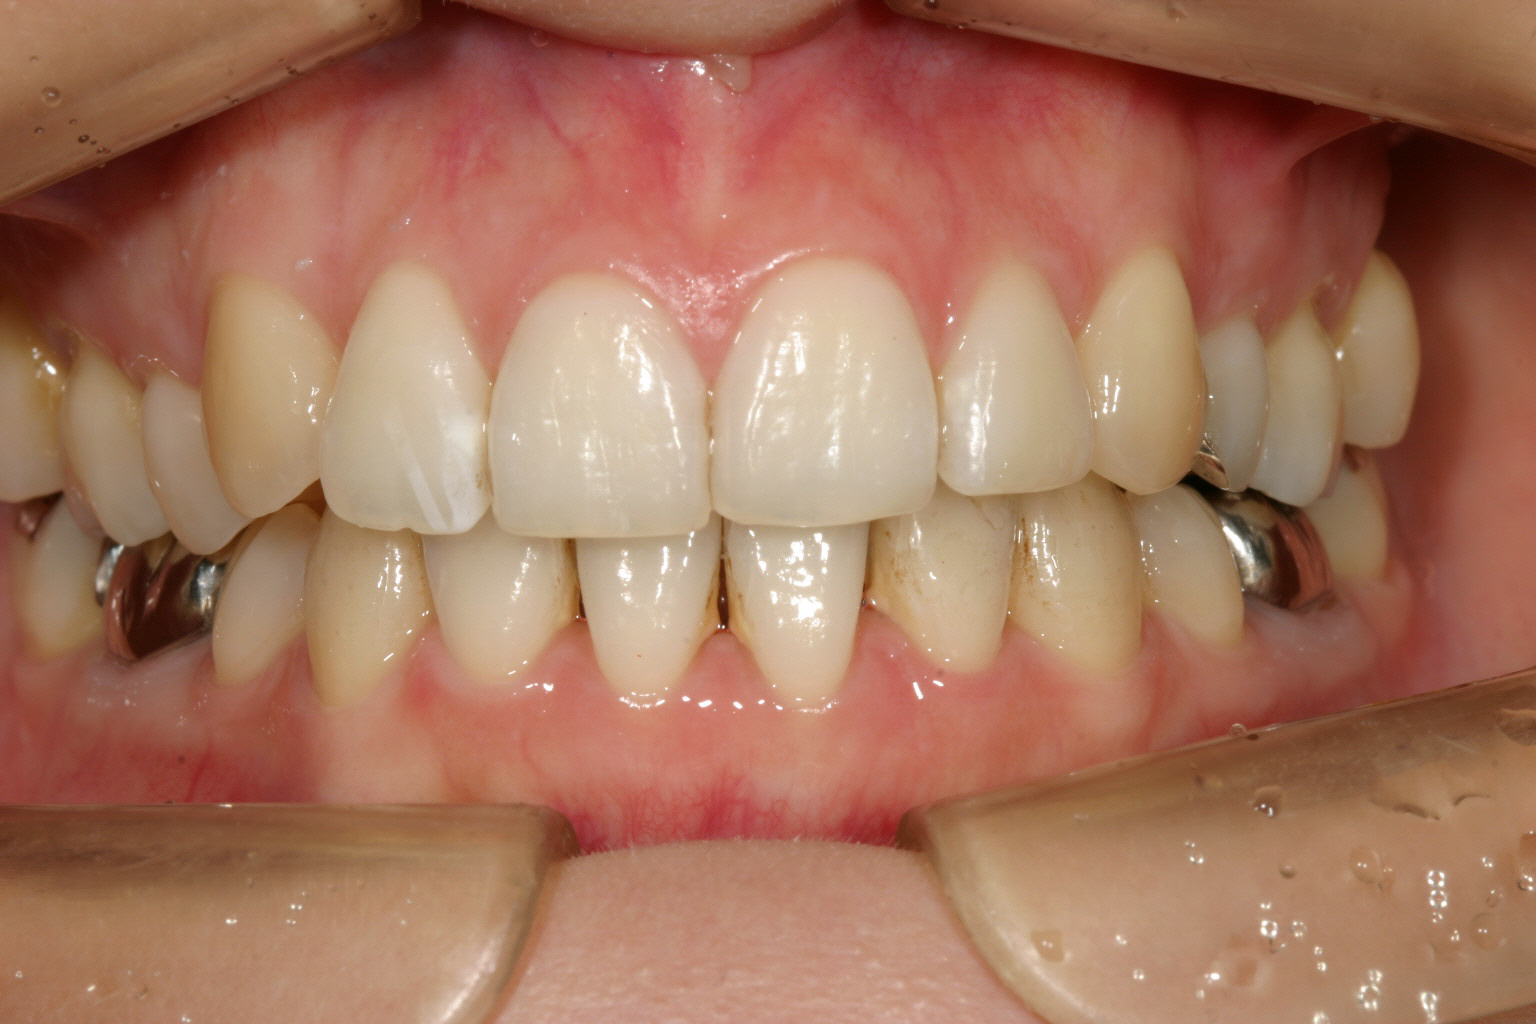

前歯のアーチの尖りを丸く仕上げました。

下顎も叢生を改善しました。

オーバージェットを綺麗に改善しました。